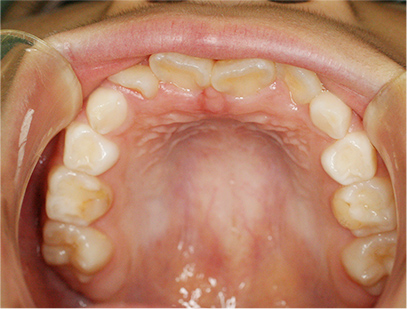

前歯の叢生(デコボコ)

前歯が並ばないことをお母さまが心配して来院されました。精査、診断の結果「前歯部の叢生」とされました。

治療計画

上下共に永久歯の萌出スペースが不足しているために、側方(横側)に拡大してスペースを作ることにしました。

取り外しのできる矯正装置

治療期間は患者様の努力とお母さまの協力が得られ6か月で終了しました。